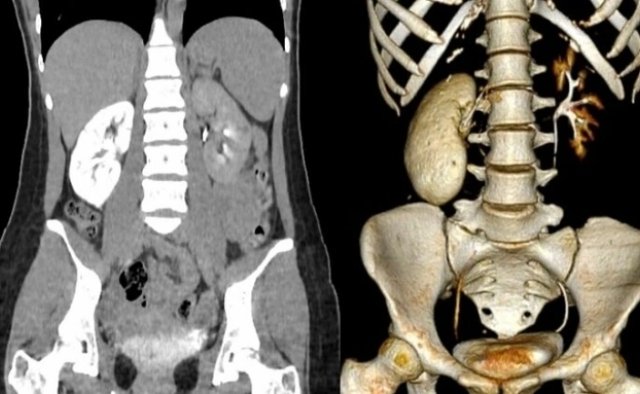

Thận 'hóa đá' khi mới 18 tuổi

Một cô gái trẻ khỏe mạnh nhập viện cấp cứu trong đêm vì thận viêm nặng từ thói quen ăn mì tôm thay cơm, nghiện...